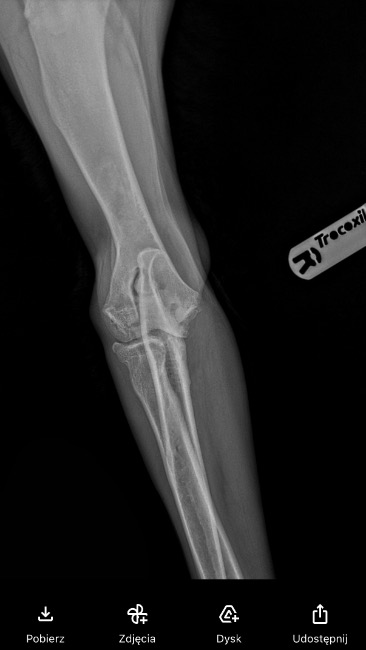

Molly regularnie uczęszczała na fizjoterapię bo lekarze dawali jej szansę „ a może jeszcze się trochę zrośnie„. Po kolejnych tygodniach/ miesiącach walki dysplazja zaczęła być widoczna gołym okiem - łopatka która „wypadała „ , wykrzywione przednie łapki - szczególnie w stawach łokciowych, jeszcze mocniejsze „rzucanie” podczas gdy pies chciał się położyć, spacery które i tak wedle zaleceń były bardzo krótkie skróciły się jeszcze bardziej, widać było że aktywnosci nawet te najprostsze sprawiały jej duży ból … oczywiście Molly cały czas przyjmowała leki i suplementację aby się tak nie męczyła..

Z góry ogromnie dziękujemy nawet za najmniejsze wpłaty oraz udostępnienia ;) zalaczam również dokumentacje medyczna